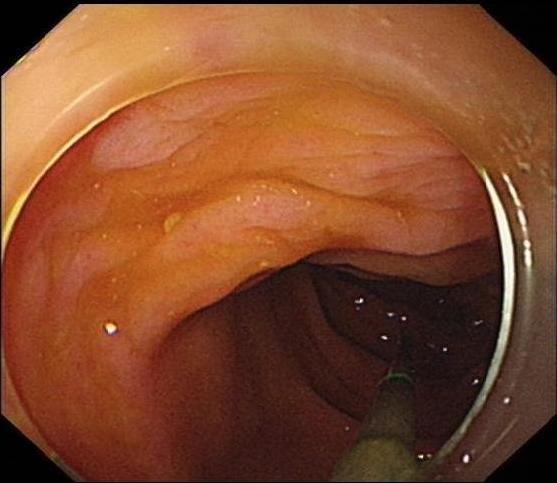

2.2 术前准备及术中配合根据无痛胃肠镜要求,对患者进行肠道准备及禁食禁饮宣教,护士加强患者心理支持,并做好仪器设备准备,如抢救车、除颤仪等。结肠镜前端置透明帽后循腔进镜,经直肠、乙状结肠、降结肠、横结肠时,见1个条形金属异物,长约3 cm(图 7),观察到一端已插入肠壁,首先选用异物钳将插入尖锐端金属轻轻拔出。为避免金属钻易脱落,强行取出异物容易造成肠道二次损伤,改用圈套器将尖锐端套住收紧后拉入透明帽内配合医生不断变换角度,调整方向,使异物方向和镜身尽量保持平行(图 8)缓慢通过各结肠弯曲部,顺利将异物取出(图 9)。整个内镜操作过程只用了15 min,无出血和穿孔等并发症发生。

| 图 8 圈套器将尖锐端套住收紧后拉入透明帽内,调整方向,使异物方向使镜身尽量保持平行,缓慢通过各结肠弯曲部 |

| 图 9 取出尖锐异物,长度约5 cm |

3 讨论结肠异物较上消化道异物、直肠异物少见,大多数为经口吞入异物,并随着肠蠕动进入至结肠。目前针对下消化道异物处理国内外暂无指南或专家共识,临床上基本按照上消化道异物处理策略开展。结肠异物的诊断主要依赖于腹部体格检查、病史采集、腹部CT/X线检查。其治疗主要根据患者的症状、异物的大小、性质及滞留位置决定[13]。吕颜智等[14]通过血清降钙素原对急性消化道出血部位进行预测,发现下消化道穿孔者血清降钙素原有较好的预测作用。可作为判断是否发生穿孔的指标之一。本例患者采用多学科联合协作,联合放射科、外科等制定诊疗和应急预案,选择最佳治疗方案,成功在内镜下取出迁移性结肠异物,无并发症的发生。护士在操作配合中需注意:(1)肠镜前端使用内镜专用透明帽,收住尖锐异物后要拉入透明帽内,与镜身保持平行(图 8),可防止异物尖端撕裂黏膜;(2)术中异物钳改用圈套器能更牢固收紧尖锐异物,防止退镜过程中因异物脱落或划伤黏膜造成二次损伤[15]。